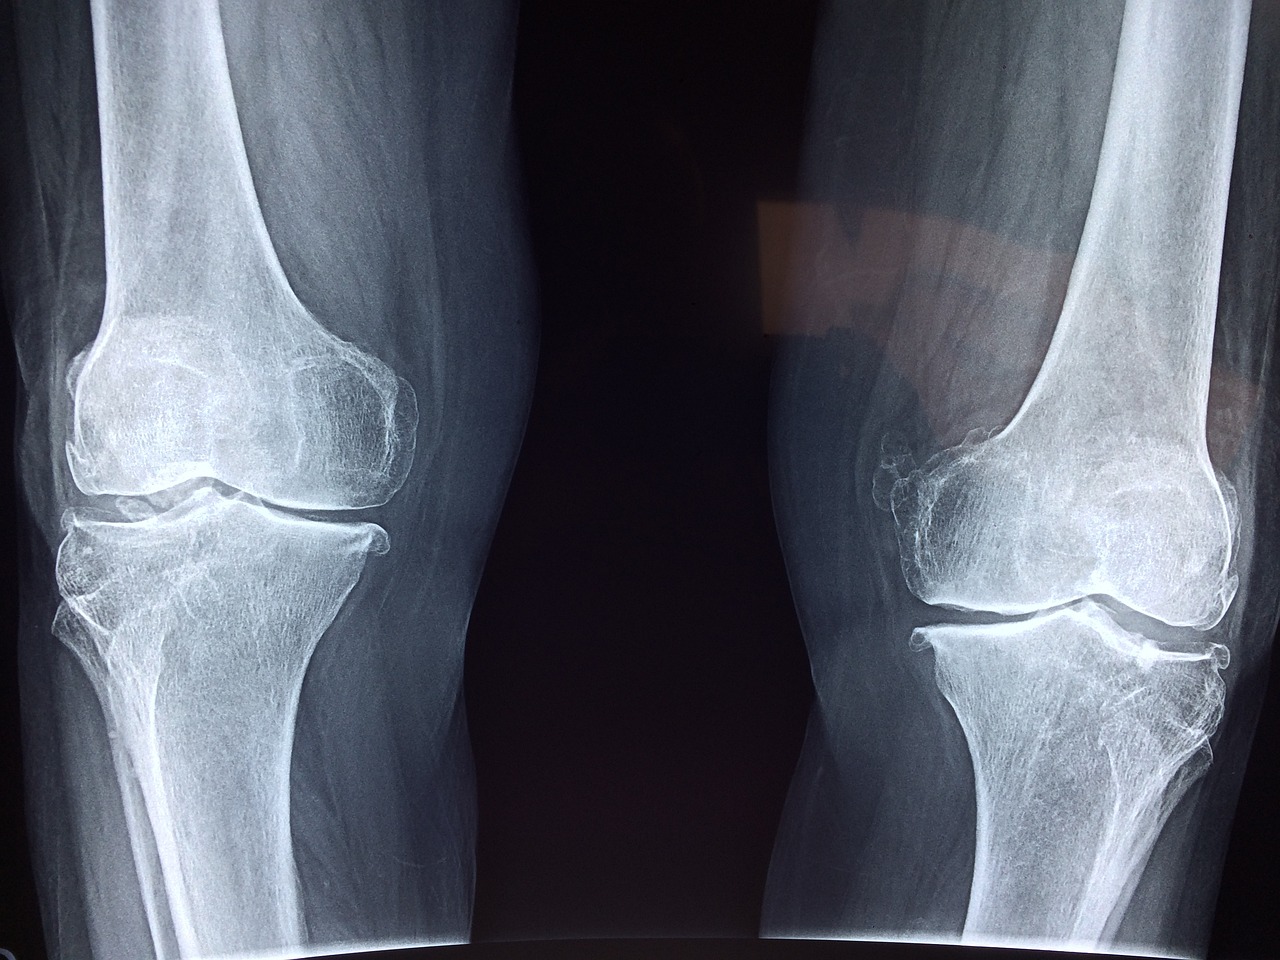

퇴행성 관절염이 진행되면 무릎이 O자형으로 변하고, X-ray 상에서 무릎 내측 연골이 닳아 뼈끼리 붙어 있는 모습을 확인할 수 있습니다. 이는 관절염 말기 상태로, 극심한 통증을 유발합니다.